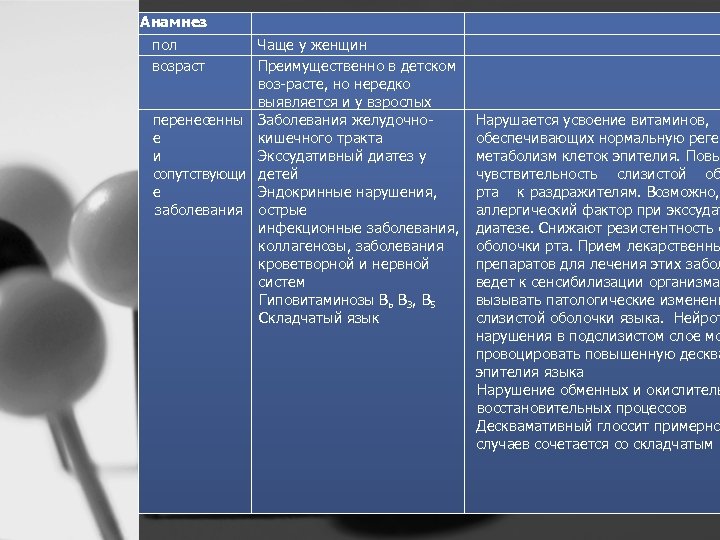

Анамнез пол возраст Чаще у женщин Преимущественно в детском воз расте, но нередко выявляется и у взрослых перенесенны Заболевания желудочно е кишечного тракта и Экссудативный диатез у сопутствующи детей е Эндокринные нарушения, заболевания острые инфекционные заболевания, коллагенозы, заболевания кроветворной и нервной систем Гиповитаминозы Вь В 3, В 5 Складчатый язык Нарушается усвоение витаминов, обеспечивающих нормальную реген метаболизм клеток эпителия. Повы чувствительность слизистой об рта к раздражителям. Возможно, аллергический фактор при экссудат диатезе. Снижают резистентность с оболочки рта. Прием лекарственны препаратов для лечения этих забол ведет к сенсибилизации организма вызывать патологические изменени слизистой оболочки языка. Нейрот нарушения в подслизистом слое мо провоцировать повышенную десква эпителия языка Нарушение обменных и окислитель восстановительных процессов Десквамативный глоссит примерно случаев сочетается со складчатым я